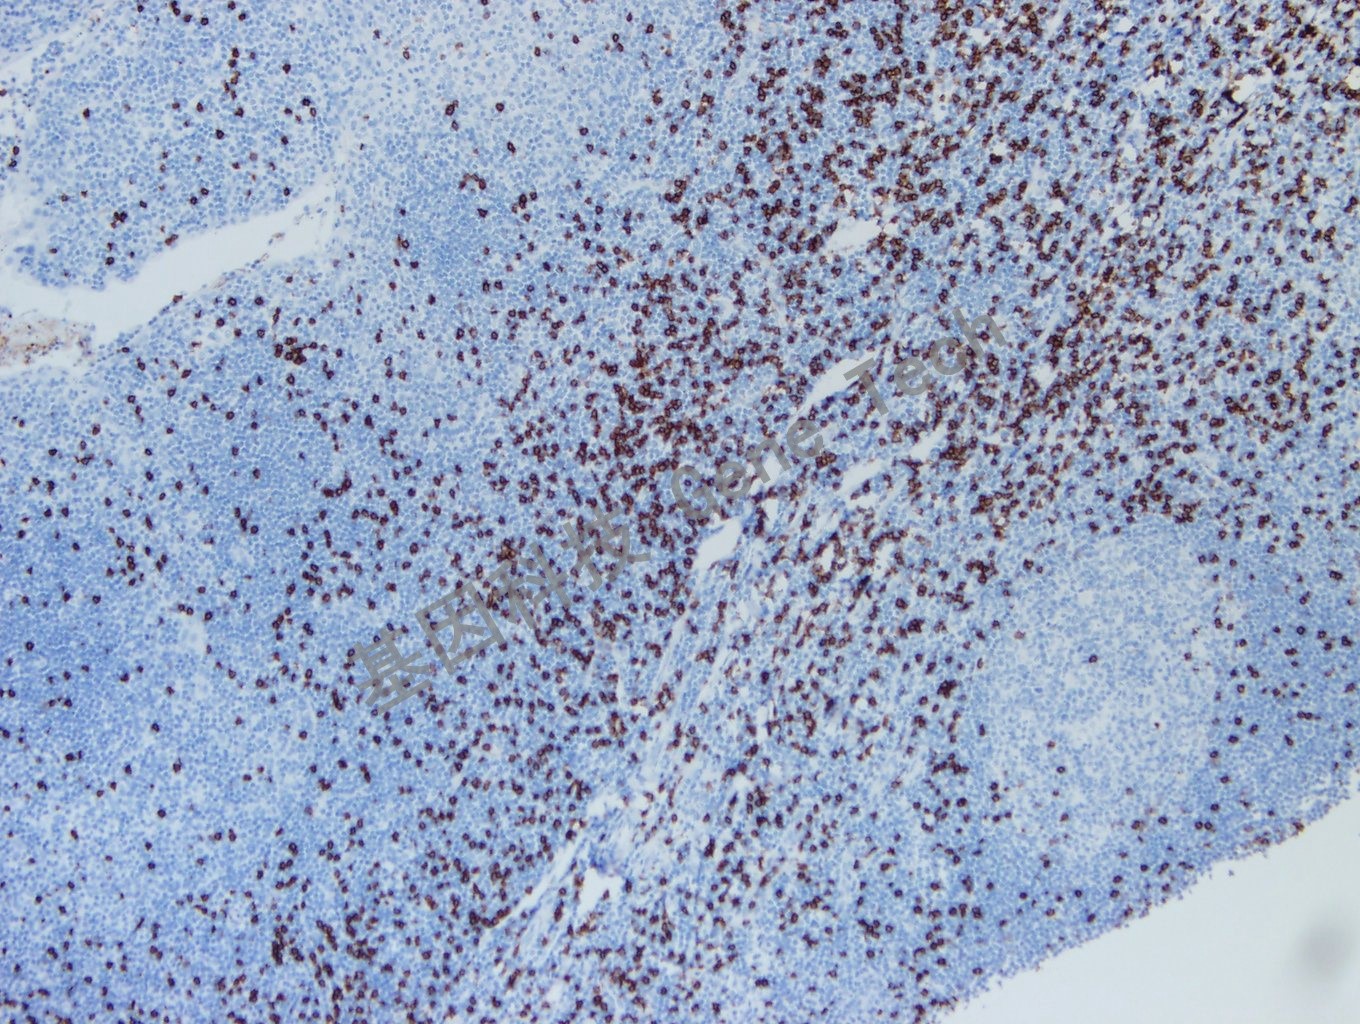

CD8 抗體 兔抗人 CD8

| 克隆號:SP16 | 陽性對照:扁桃體/淋巴結(jié) | 陽性部位:細(xì)胞膜 |

| 預(yù)處理:高pH熱修復(fù) | 適用:石蠟切片/冰凍切片 | 顯色系統(tǒng):GTvisionTM |

| 簡介:CD8 分子是存在于抑制//細(xì)胞毒性T 細(xì)胞表面的32kDa 的糖蛋白,為MHC- Ⅰ類分子受體。用于標(biāo)記抑制/ 細(xì)胞毒性T 細(xì)胞及NK 細(xì)胞,也可用于前驅(qū)T 淋巴母細(xì)胞白血病或淋巴瘤的標(biāo)記。與CD4 聯(lián)用,計算CD4/CD8 比值,對于某些疾病的診斷、治療及預(yù)后都有一定意義。 | ||

| 扁桃體石蠟切片,用 CD8(GT2112)染色,細(xì)胞膜陽性,DAB 顯色。 | ||